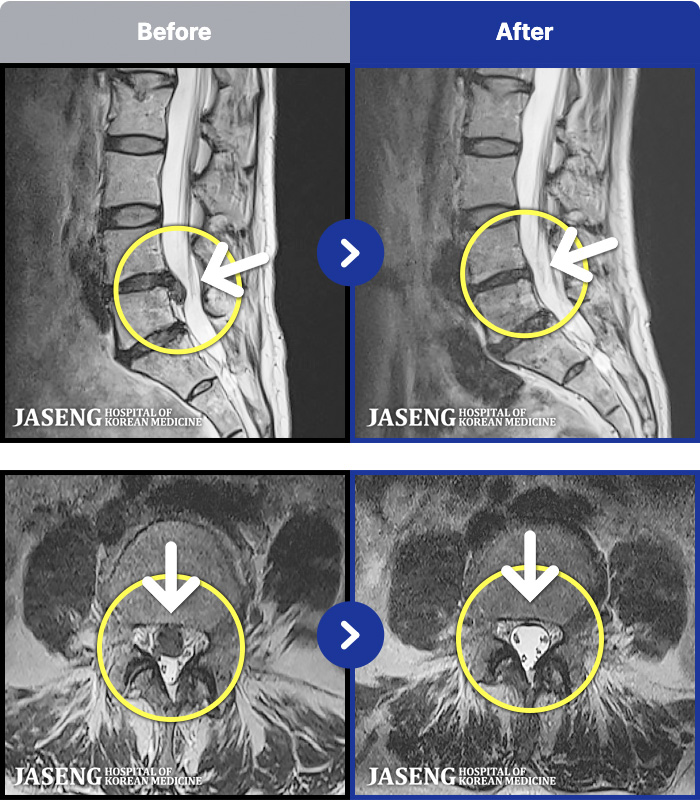

1,297 MRI ũ ʸ Ȯϼ.